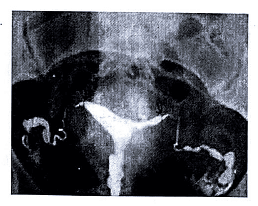

• Hysterosalpingography